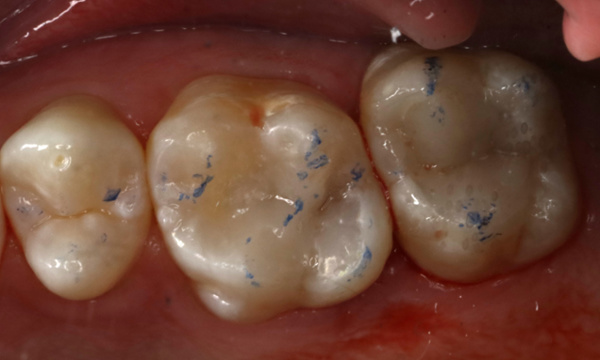

Composite bonding fillings restoring decayed molars

These molars were very heavily decayed. We placed composite fillings to restore them to their previous shape and function. Root canal treatment was avoided by keeping the nerve alive. This patient also chose to have crowns on these teeth a few years after, to provide a stronger long term solution.